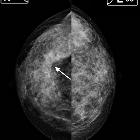

The tent sign is a term referring to a characteristic appearance of the posterior edge of the breast parenchyma when a mass (usually an infiltrating lesion) causes its retraction and forms an inverted "V" that resembles the tip of a circus tent.

The detection of a "tent sign" is facilitated by the systematic reading of mammograms with the technique of masking.